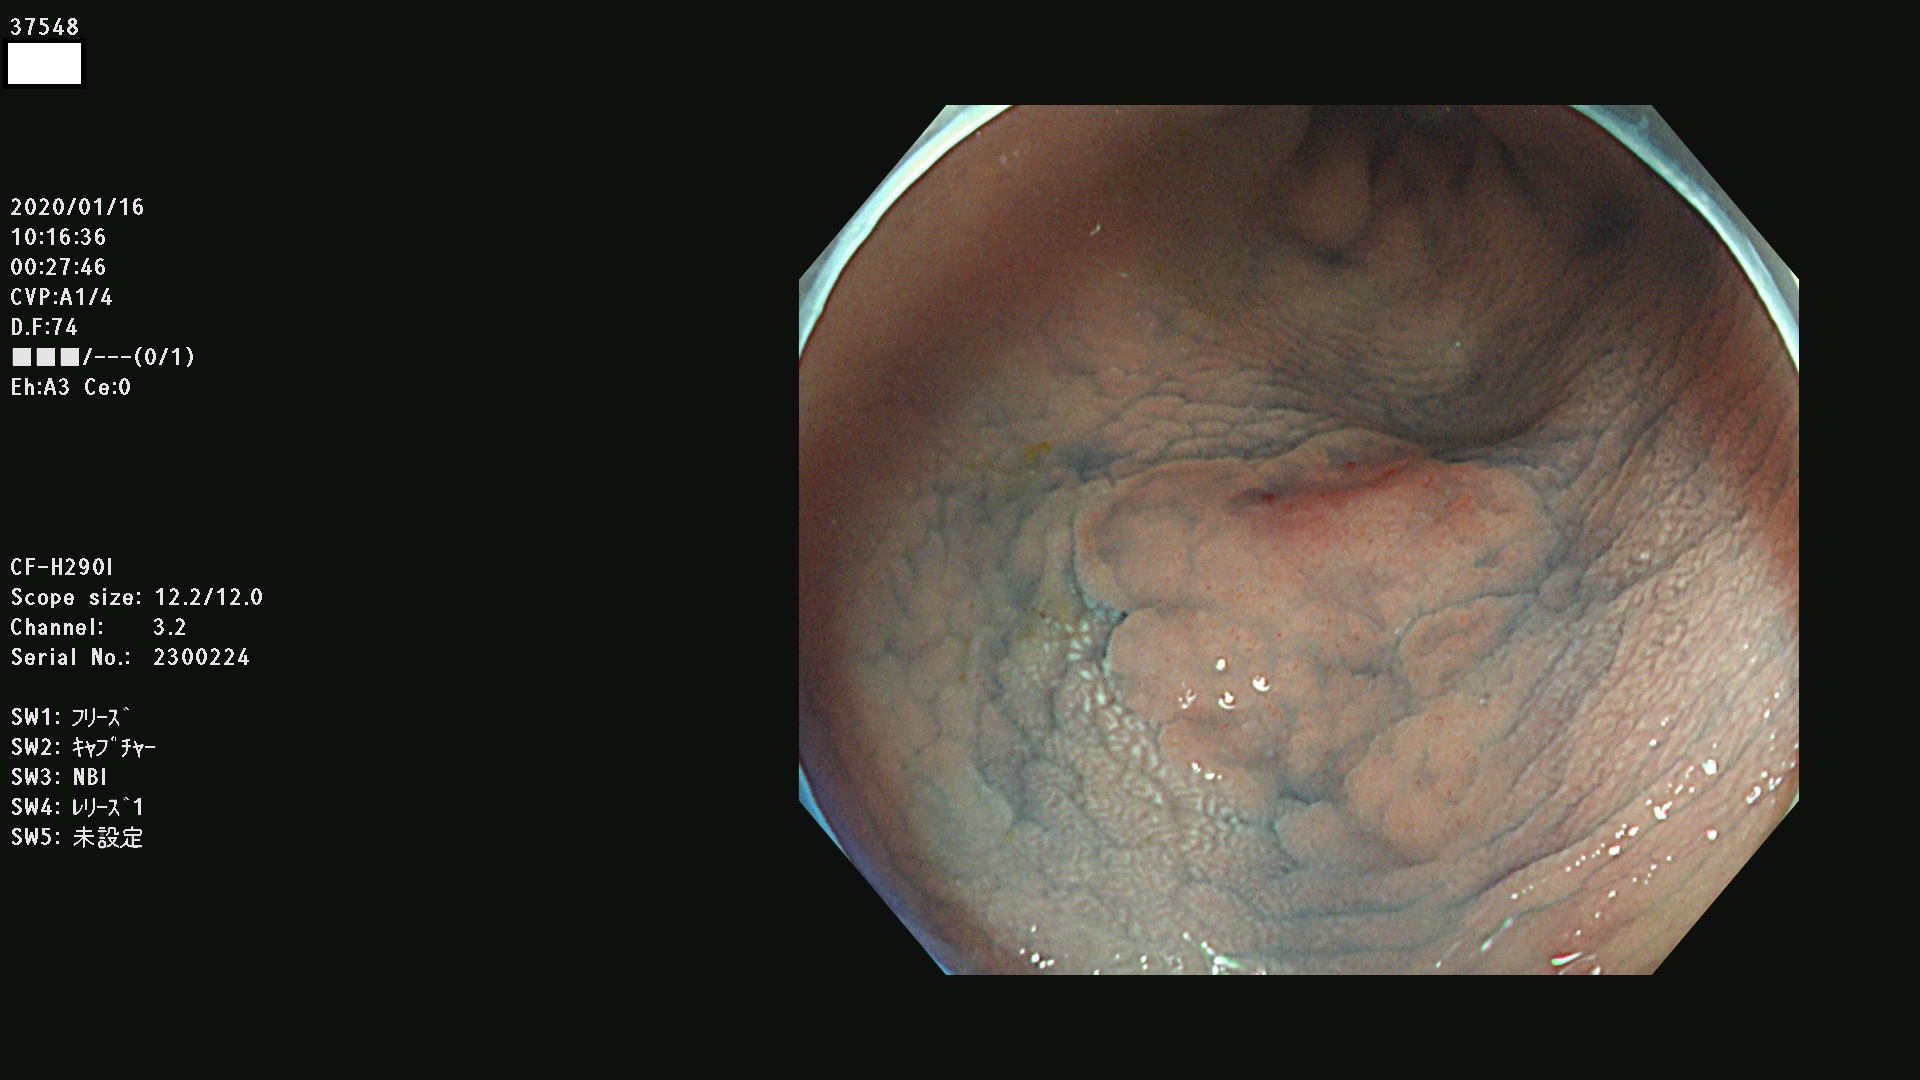

発見困難で危険性の高い平坦型病変(上記100名より抽出) ![]()